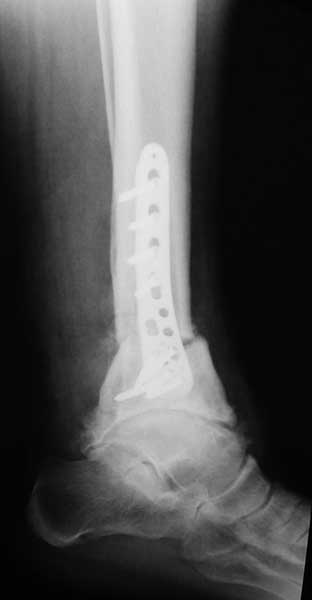

У пациентки резко выраженная вальгусная деформация стопы. При попытке выполнения артродеза без коррекции оси конечности вероятность несостоятельности артродеза и сохранения болей крайне велика. Артроз имеет односторонний характер и связан, с большой степенью вероятности, с нарушением оси конечности. При восстановлении правильной оси такой сустав сможет послужить еще не один год. В плане дообследования обязательны снимки в переднезадней проекции под нагрузкой с захватом бугра пяточной кости, которые помогут лучше оценить осевые взаимоотношения голени и стопы. Исправить эти взаимоотношения можно, как путем медиализирующей остеотомии пяточной кости, так и путем остеотомии большеберцовой кости. Сохраняющая голеностопный сустав хирургия сейчас на подъеме, ей посвящаются симпозиумы, статьи. Она служит, как для сохранения сустава, так и для подготовки последующих успешных операций артродезирования или протезирования.

Во вложении - пример операции при гораздо более грубом посттравматическом артрозе, позволившей пациенту 61 г. через 1.5 г. после корригирующей остеотомии не думать о следующем вмешательстве. Хотя, есть работы, показывающие, что максимальный эффект после подобных остеотомий развивается к двум годам.

Красиво конечно, но верится с трудом , что с таким артрозом пациента перестали беспокоить боли и ограничение движений в суставе. Возможно я и ошибаюсь.

При чем тут ограничение движений когда речь идет об артродезе? Конечно ограничение осталось. А вот боли уменьшились на порядок. И стопа стала на место. Во всяком случае, сейчас вопрос об операции не стоит. А если встанет, то можно будет гораздо проще и с большей степенью вероятности получения положительного результата выполнить артродез. Но на самом деле артрозы голеностопного сустава при правильной оси конечности часто протекают очень благоприятно даже при далеко зашедших стадиях.